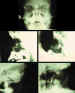

La utilización de Rayos X (figura 15) con proyecciones Caldwell, Waters, o las antero-posteriores pueden demostrarnos la presencia, pero no la localización, de un CEIO radiopaco y no detectará CEIO radiotransparentes, como la madera o el cristal. La ecografía nos ofrece una mejor localización del CEIO y es esencial para obtener información acerca de otros cambios estructurales como desprendimientos de retina o coroides. Al realizar esta exploración, han de tomarse precauciones para no comprimir el globo, sobretodo en los que presentan grandes heridas, y no producir prolapsos adicionales de su contenido. La ecografía con un estudio sistemático, con abordaje transversal y longitudinal puede determinar la localización del CEIO. La ultrasonografía biomicroscópica nos aporta algo más a la hora de diagnosticar cuerpos extraños ocultos o de polo anterior (123-125). La tomografía computerizada (TC) es el método diagnóstico de elección porque localiza y detecta CEIO radiopacos y radiotransparentes en 3 dimensiones. La TC tiene ciertas limitaciones y los CEIO metálicos crean artefactos significativos, que pueden dificultar la localización exacta. Esto puede ser un inconveniente a la hora de determinar si la localización de un CEIO es intrarretiniana o intraescleral. Asímismo la TC puede presentar problemas a la hora de identificar algunos CEIO de baja densidad, como la madera. Chacko, nos presenta en su artículo una interesante comparación entre la Tomografía Computerizada clásica (figura 16) y el TAC helicoidal (figura 17), demostrándose esta última más eficaz para la localización espacial de cuerpos extraños intraoculares o intraorbitarios (126).

63-15.jpg (11228 bytes)

Figura 15. Las distintas proyecciones de una radiografía de órbita, nos demuestran la presencia de cuerpos extraños radiosensibles, pero no la localización.

63-16.jpg (11435 bytes)

Figura 16. Perdigón que pasa a través del ápex orbitario destrozando el nervio óptico.

63-17.jpg (11175 bytes)

Figura 17. La tomografía computerizada (TC) es el método diagnóstico de elección porque localiza y detecta CEIO radiopacos y radiotransparentes en 3 dimensiones.